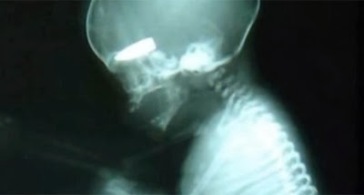

طلقة تُدخل «جنين» التاريخ كأصغر ضحية في سوريا

عرضت صحيفة “ديلي ميل” البريطانية تقريراً يبرز أصغر ضحية شهدتها الصراعات المأساوية في سوريا وهو جنين لم ير النور بعد.